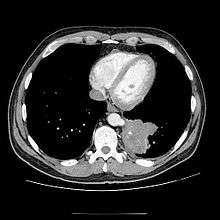

CT

Chest CT showing pulmonary sequestration